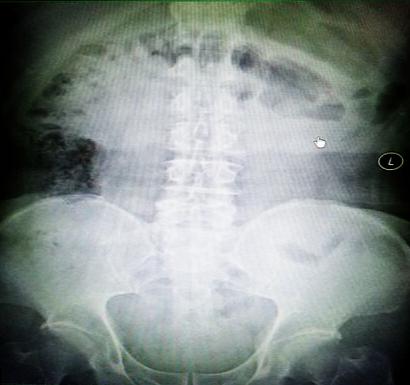

受試患者在結腸端端吻合術中,使用我司新研制產品達到了理想的預期效果。患者術后7天、14天X光片顯影,可降解腸道支架均能按研制設計的預期時間節點保持應有強度,術后21天X光片顯示可降解腸道支架已完全破碎,并排出體外。在整個試驗過程中,病患無任何不良反映,耐受良好。